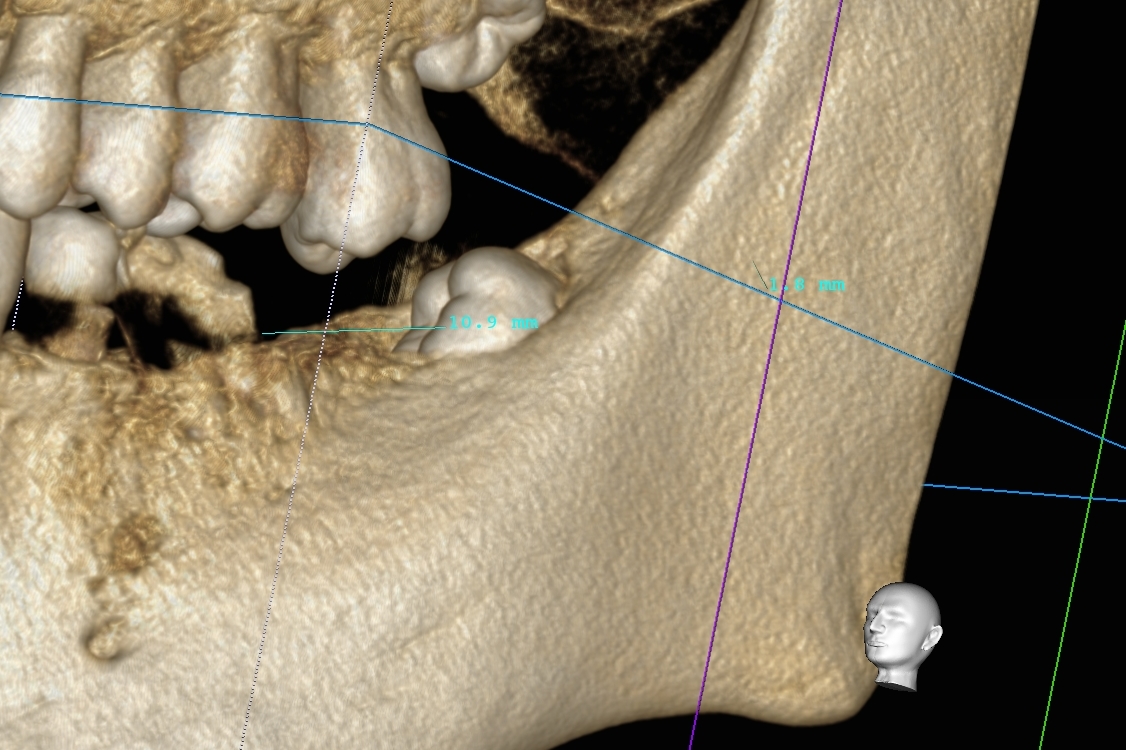

そして、歯周資本治療が終了し、いざ右下のインプラント治療を行ったレントゲン所見を以下に示します。

【右下(画面向かって左下2本です)のインプラント埋入手術】

インプラント手術に関して、術後合併症がないよう、神経損傷などおこさないよう術前にCT精密検査を行い、手術用の埋入キットを作製してOPEを行っております。手術は麻酔が終了して30分程度です。今まで多数のインプラント経験があるため、これぐらいの時間で終了することがほとんどです(*^-^*)